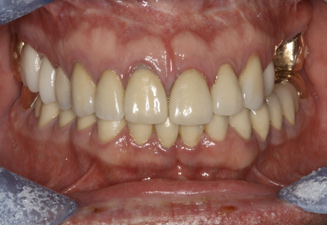

Fig 13. An All-on-4 approach was used to treat both arches with interim immediate and eventual definitive restorations.

Figure 13

Fig 14. Final restorations used for 6-1/2 additional years.

Figure 14

This is an unfortunate mindset in that current advances in protocol and technology can result in significant advantages in addressing some or most of these concerns. The patient shown in Figure 12 may serve to illustrate this point. She had a destroyed maxillary dentition, a less-compromised but highly unesthetic mandibular component, and a single goal: to be able to "smile at my grandchildren again." In consultation with her and her family, it was decided that a double-arch fixed implant approach would most realistically address her esthetic goals and provide her with the desired prosthetic result. She was 102 years old at the time of initial consultation. Using a staged operating-room approach, provisional restorations were initially delivered, followed by subsequent definitive hybrid final restorations. She was able to use these comfortably for the next 6-½ years (Figure 13 and Figure 14).